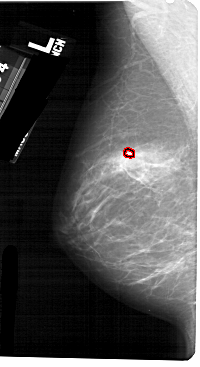

A_1268_1.LEFT_CC

LEFT_CC LINES 5371 PIXELS_PER_LINE 2671 BITS_PER_PIXEL 12 RESOLUTION 43.5 OVERLAY

FILE: A_1268_1.LEFT_CC.OVERLAY

TOTAL_ABNORMALITIES 1

ABNORMALITY 1

LESION_TYPE CALCIFICATION TYPE PLEOMORPHIC DISTRIBUTION CLUSTERED

ASSESSMENT 4

SUBTLETY 4

PATHOLOGY BENIGN

TOTAL_OUTLINES 1

BOUNDARY